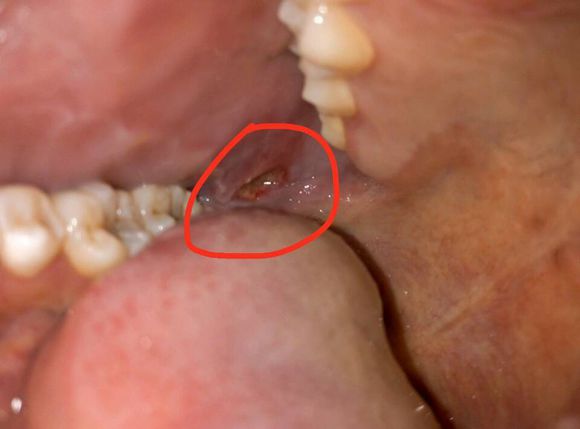

当出现口腔溃疡后首先要注意溃疡的程度,一定要先排除恶性溃疡的可能,其中恶性溃疡面积大,中间深深凹陷,边缘凸起,用洗干净的手指按压,手感有点硬,这个时候应该立即就医治疗。

对于浅表的溃疡,一定要注意口腔卫生,尽量避免细菌感染,平时可用淡盐水漱口来消炎。一般会很快治愈。